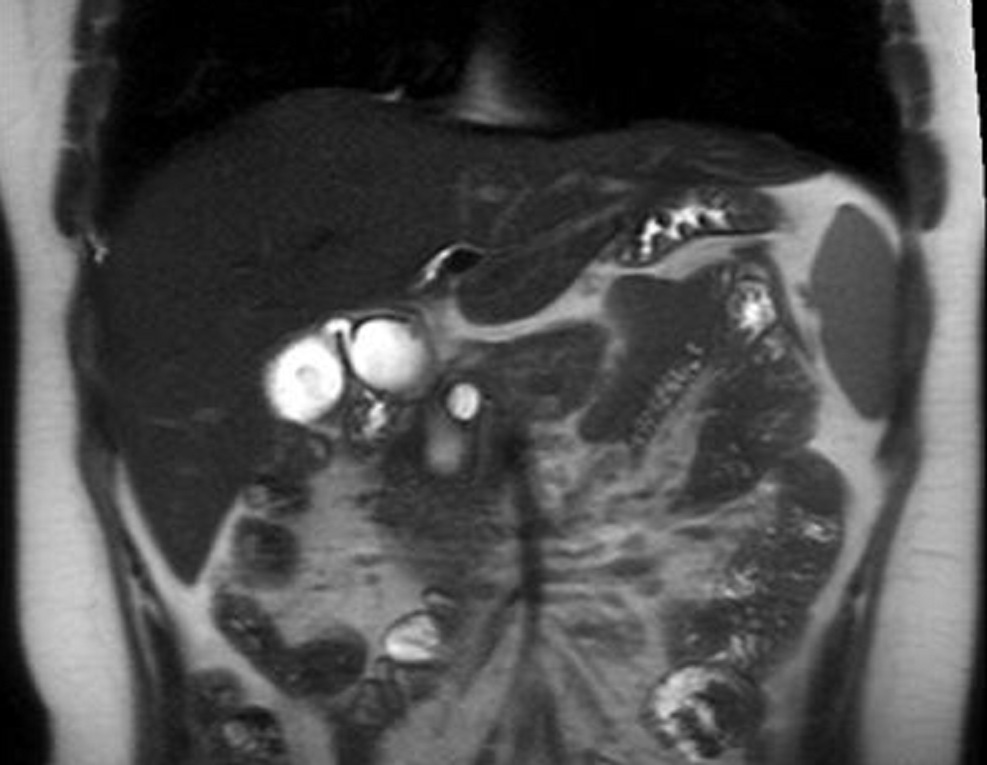

Sus les coupes IRM pondere

sur T2 Image radiolofique des TIPMP de type canaux

secondaire sont des kystes unique ou multiple

arondie ou ovalaire polylobulaire de fortement

hyperintense et comunication souvent avec canal

principale CPP ( fleche rouge ) . Image radiologique

IRM ponderation sur T2 , en coupe axiale |